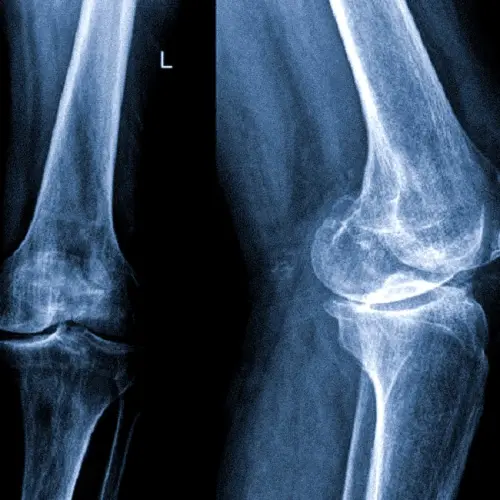

По наблюдениям в практике, УЗД колінного суглоба у Києві часто виявляє приховані пошкодження меніска, які не проявляються на рентгені. У порівнянні з рентгенографією, метод має перевагу у візуалізації м'яких тканин і не несе променевого навантаження.

Що показує УЗД суглобів? За допомогою цього методу діагностики можна виявити широкий спектр патологій, включаючи пошкодження зв'язок та сухожиль, запалення, дегенеративні зміни хрящової тканини та наявність рідини в порожнині суглоба. Точність УЗД суглобів досягає 95%.